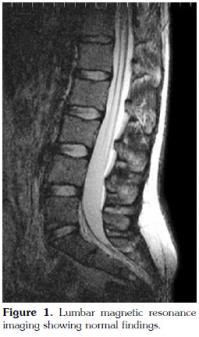

There were no abnormal findings of the lumbar spine on magnetic resonance imaging (MRI) (Figure 1). Contrast enhanced sacroiliac MRI revealed lobulated, multivesicular cystic lesions, which originated from the second sacral vertebra, extending to the sacral ala and iliac wing at the third sacral level, which also filled the sacroiliac joint. Vesicular lesions in the sacroiliac joint and piriform muscles showed increased contrast uptake (Figure 2). Given the patient's medical history, bone hydatid disease and other cystic bone lesions were included in differential diagnosis.